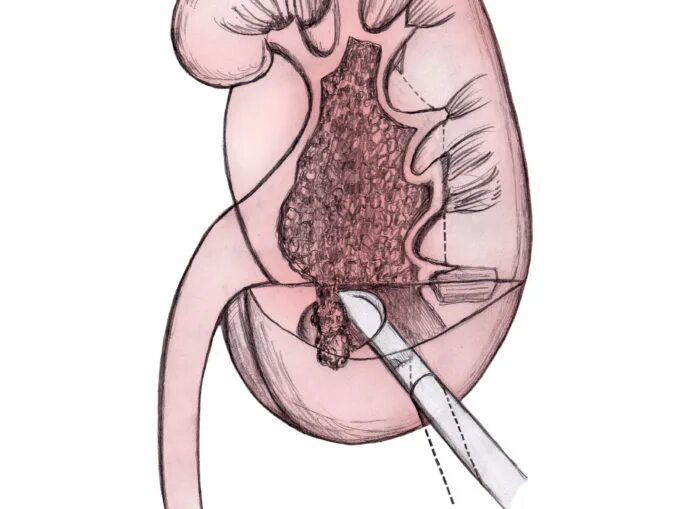

Нефростома в почке что это